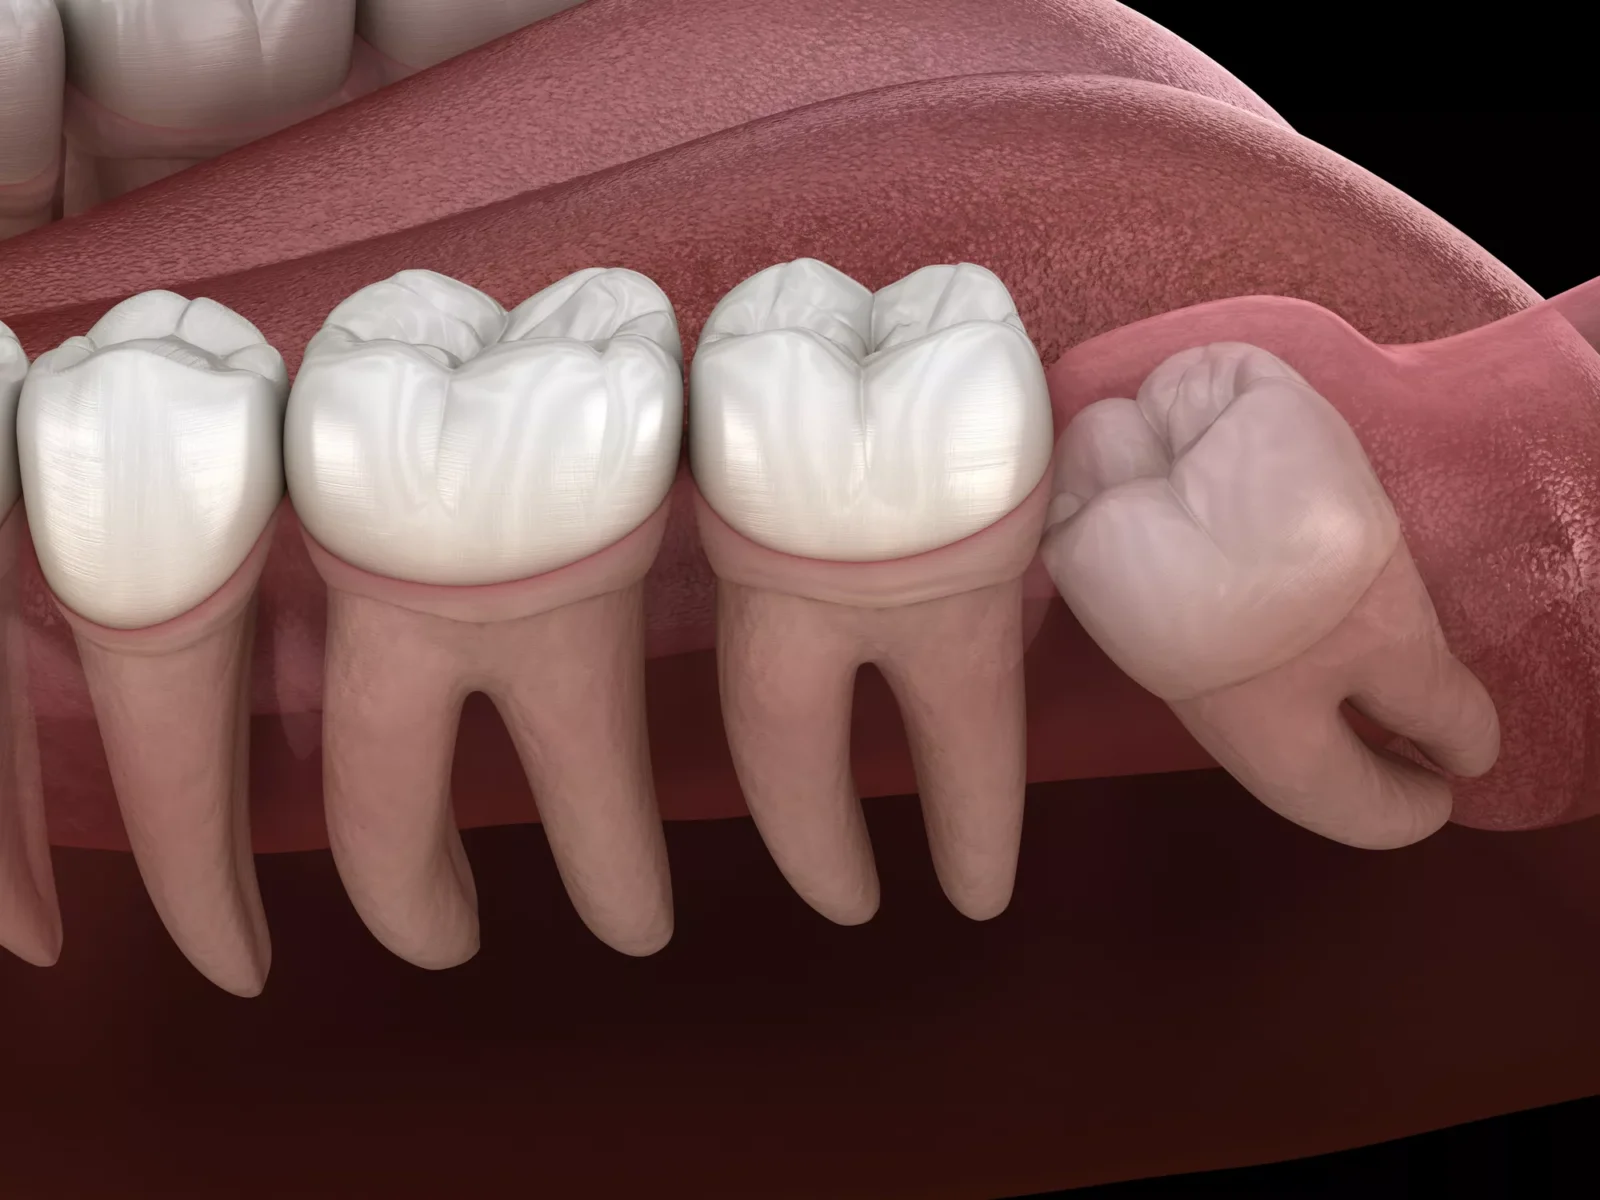

Wisdom teeth were once essential for our ancestors’ diets, but today they often cause more harm than good. Modern jaws are typically smaller, leaving little room for these extra molars to grow in properly.

Impacted wisdom teeth can cause ongoing pain, infections, cysts, and damage to neighboring teeth. Leaving them untreated often leads to more complicated dental problems in the future.